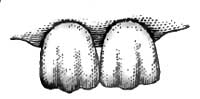

| 12. | NOTCHING OF SYPHILITIC INCISOR TEETH |

| 13. | OÏDIUM ALBICANS FROM THE MOUTH IN A CASE OF THRUSH |